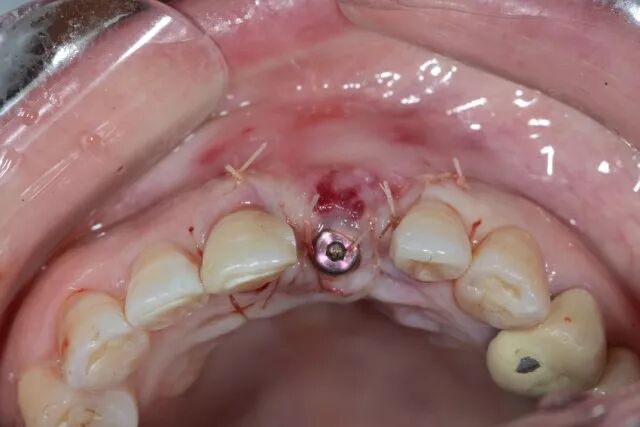

二期植入種植體

?

覆蓋軟組織修復(fù)膜

5.0線縫合 唇側(cè)

鄂側(cè)